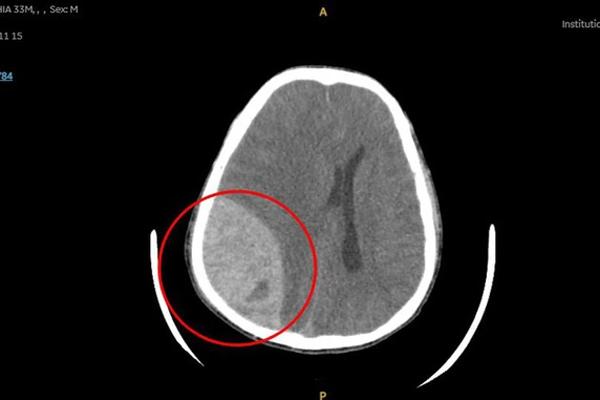

Khối máu tụ đã được lấy đi hoàn toàn và cầm máu, Ảnh:BVCC

Sau gần 3 giờ phẫu thuật căng thẳng, ca mổ đã kết thúc thành công. Sau phẫu thuật, anh N. tiếp tục được hồi sức tích cực cũng như chăm sóc toàn diện tại Khoa ICU.